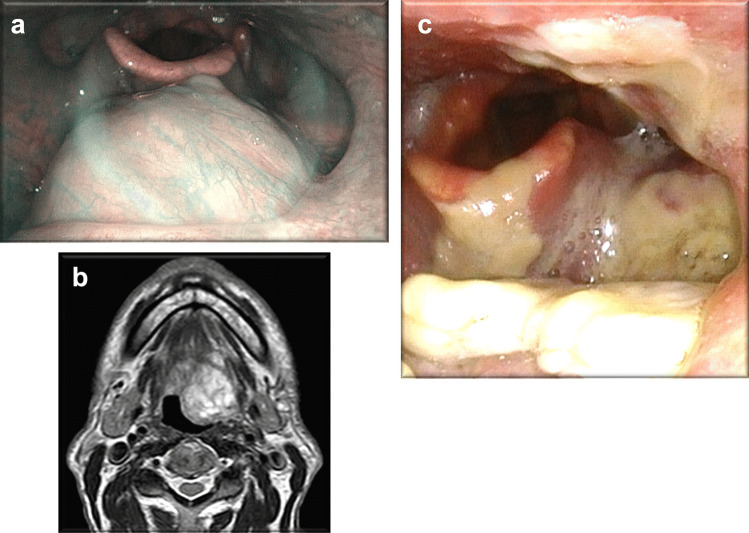

Fig. 4.

Case #4: Submucosal lesion on the left of base tongue, with a rich vascular network on covering mucosa on NBI laryngoscopy (a) and T2 scan axial magnetic resonance showing oval lesion with regular margins and homogeneous contrast medium (b), laryngoscopic image one week after surgery (c)